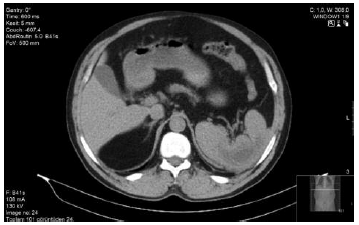

A 48-year-old male patient who had renal transplant 3 years earlier presented with left upper abdominal pain and fever. Splenomegaly and splenic ischemia without any cystic areas were seen on ultraso-nography and magnetic resonance imaging. During follow-up, a cystic lesion with a diameter of 16 × 14 cm appeared in the spleen, but a lack of apparent complaints resulted in a “watch and wait” protocol. At 1-month follow-up, pain symptoms had gradually increased, white blood cell count was 24 900/mm3, and C-reactive protein level was 14 mg/L. A computed tomography scan in the patient revealed a splenic abscess of 25 × 20 cm extending from the upper pole of the spleen to the pelvis (Figure 1). Polyoma hominis 1 (BK) virus, cytomegalovirus, Epstein-Barr virus, and parvovirus B19 polymerase chain reaction results, as well as echinococcus enzyme-linked immunosorbent assay tests, were negative.

Figure 1. Preoperative Contrast-Enhanced Computed Tomography Revealed 25 × 20 cm Spleen Abscess